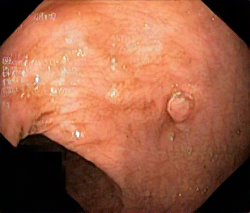

We have used a polyp dataset published with HyperKvasir dataset [51], which consists of polyp findings extracted from endoscopy examinations. HyperKvasir contains polyp images with corresponding segmentation masks annotated by medical experts. We use only this polyp dataset as a case study because of the time and resource-consuming training process of the SinGAN-Seg pipeline. However, the SinGAN-Seg model and pipeline can be used for any segmentation dataset.

A few sample images and the corresponding masks of the polyp dataset in HyperKvasir are shown in Fig 2. The polyp images are RGB images. The masks of the polyp images are single-channel images with white () for true pixels, which represent polyp regions, and black () for false pixels, which represent clean colon or background regions. In this dataset, there are different sizes of polyps. The distribution of polyp sizes as a percentage of the full image size is presented in the histogram plot in Fig 3, and we can observe that there are more relatively small polyps compared to larger polyps. Additionally, a subset of this dataset was used to prove that the performance of segmentation models trained with small datasets can be improved using our SinGAN-Seg pipeline, and the whole dataset was used to show the effect of using SinGAN-Seg generated synthetic images instead of a large dataset which has enough data to train segmentation models. In this regard, this dataset was used for two purposes: